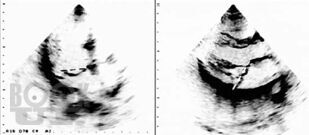

Методическое пособие посвящено одной из важнейших патологий современной кардиологии — первичному пролапсу митрального клапана и его роли в популяции. Подробно представлены основные патологические процессы, приводящие к развитию пролапса, его последствия для сердца, варианты лечения, до и послеоперационного ведения пациентов.

Особое внимание уделено эволюции критериев пролапса митрального клапана, использованию алгоритмов, исключающих гипердиагностику самой аномалии и сопутствующих осложнений. Так как основное значение в прогнозе заболевания имеет степень регургитации на клапане, которая может возрастать при физической нагрузке, обсуждаются вопросы проведения нагрузочных тестов с эхокардиографией, а также варианты допустимой физической активности пациентов.

Издание содержит многочисленные рисунки и схемы, иллюстрирующие расстройства гемодинамики, результаты исследования сердца и современные оперативные вмешательства при данной патологии.